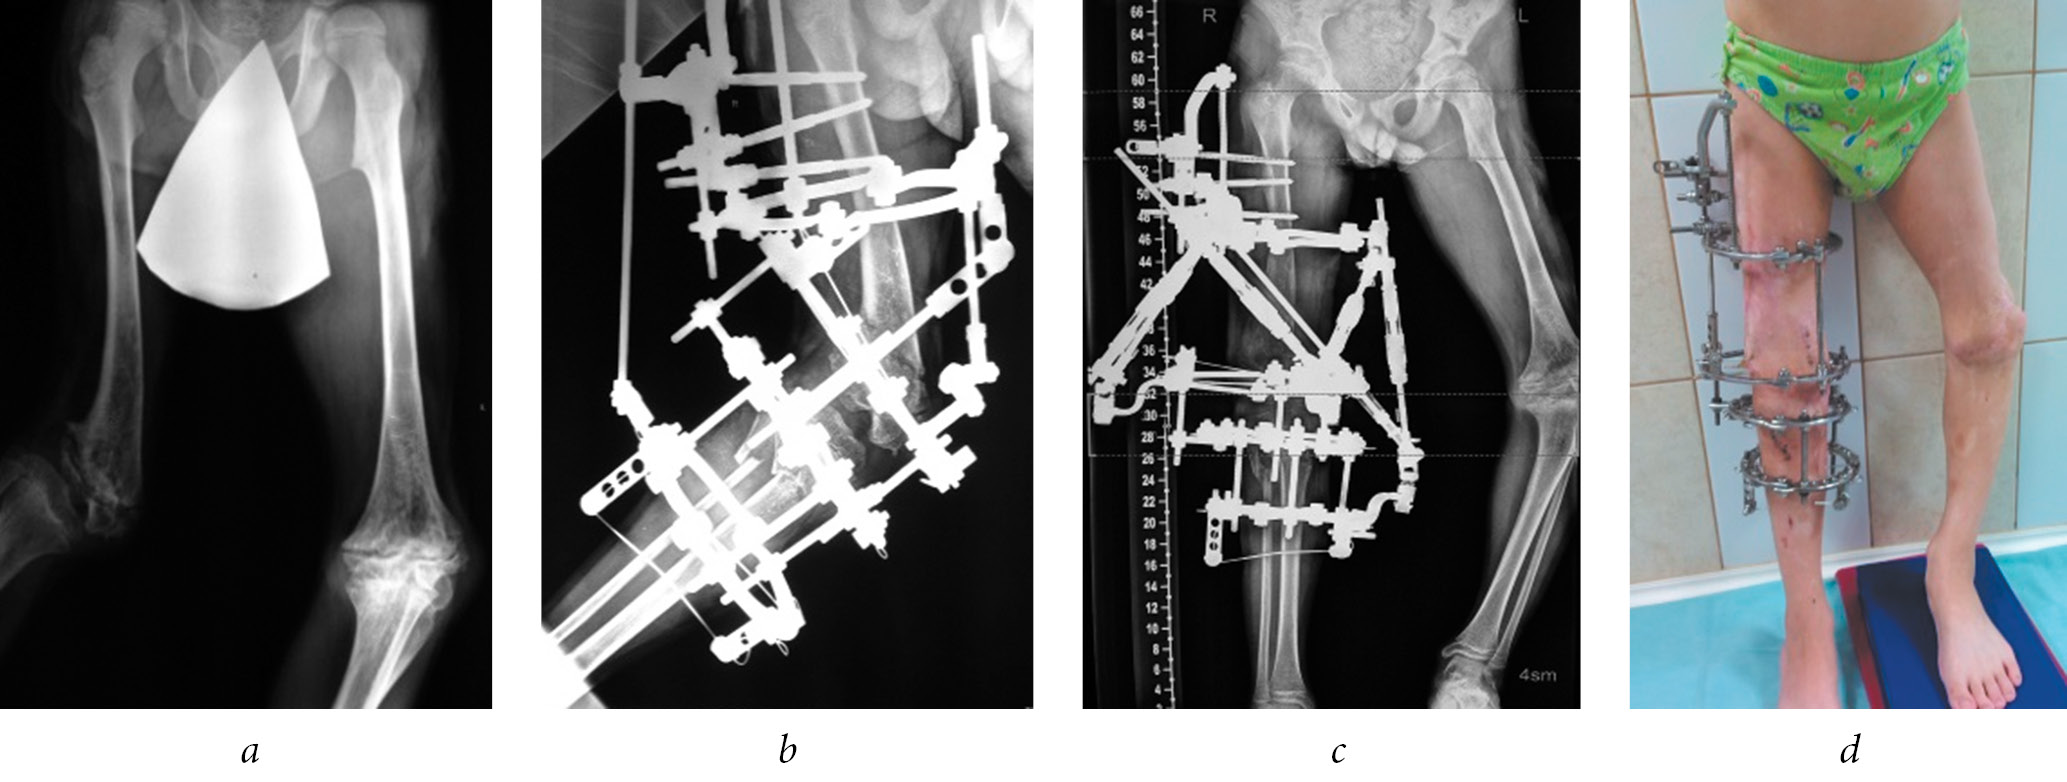

In four (33.3%) patients, the deformity correction was performed according to the controlled growth method by temporary epiphysiodesis of the actively functioning part of the bone growth zone with eight-shaped plates. Of which, the marginal synostosis of the growth zone was resected with subsequent hemiepiphysiodesis in two (16.7%) patients (Fig. 2).

Fig. 2. Resection of synostosis of the proximal growth zone of the left tibia (a) and variants of hemiepiphysiodesis of the functioning sections of the growth zones of the femur and tibia with eight-shaped plates (b)